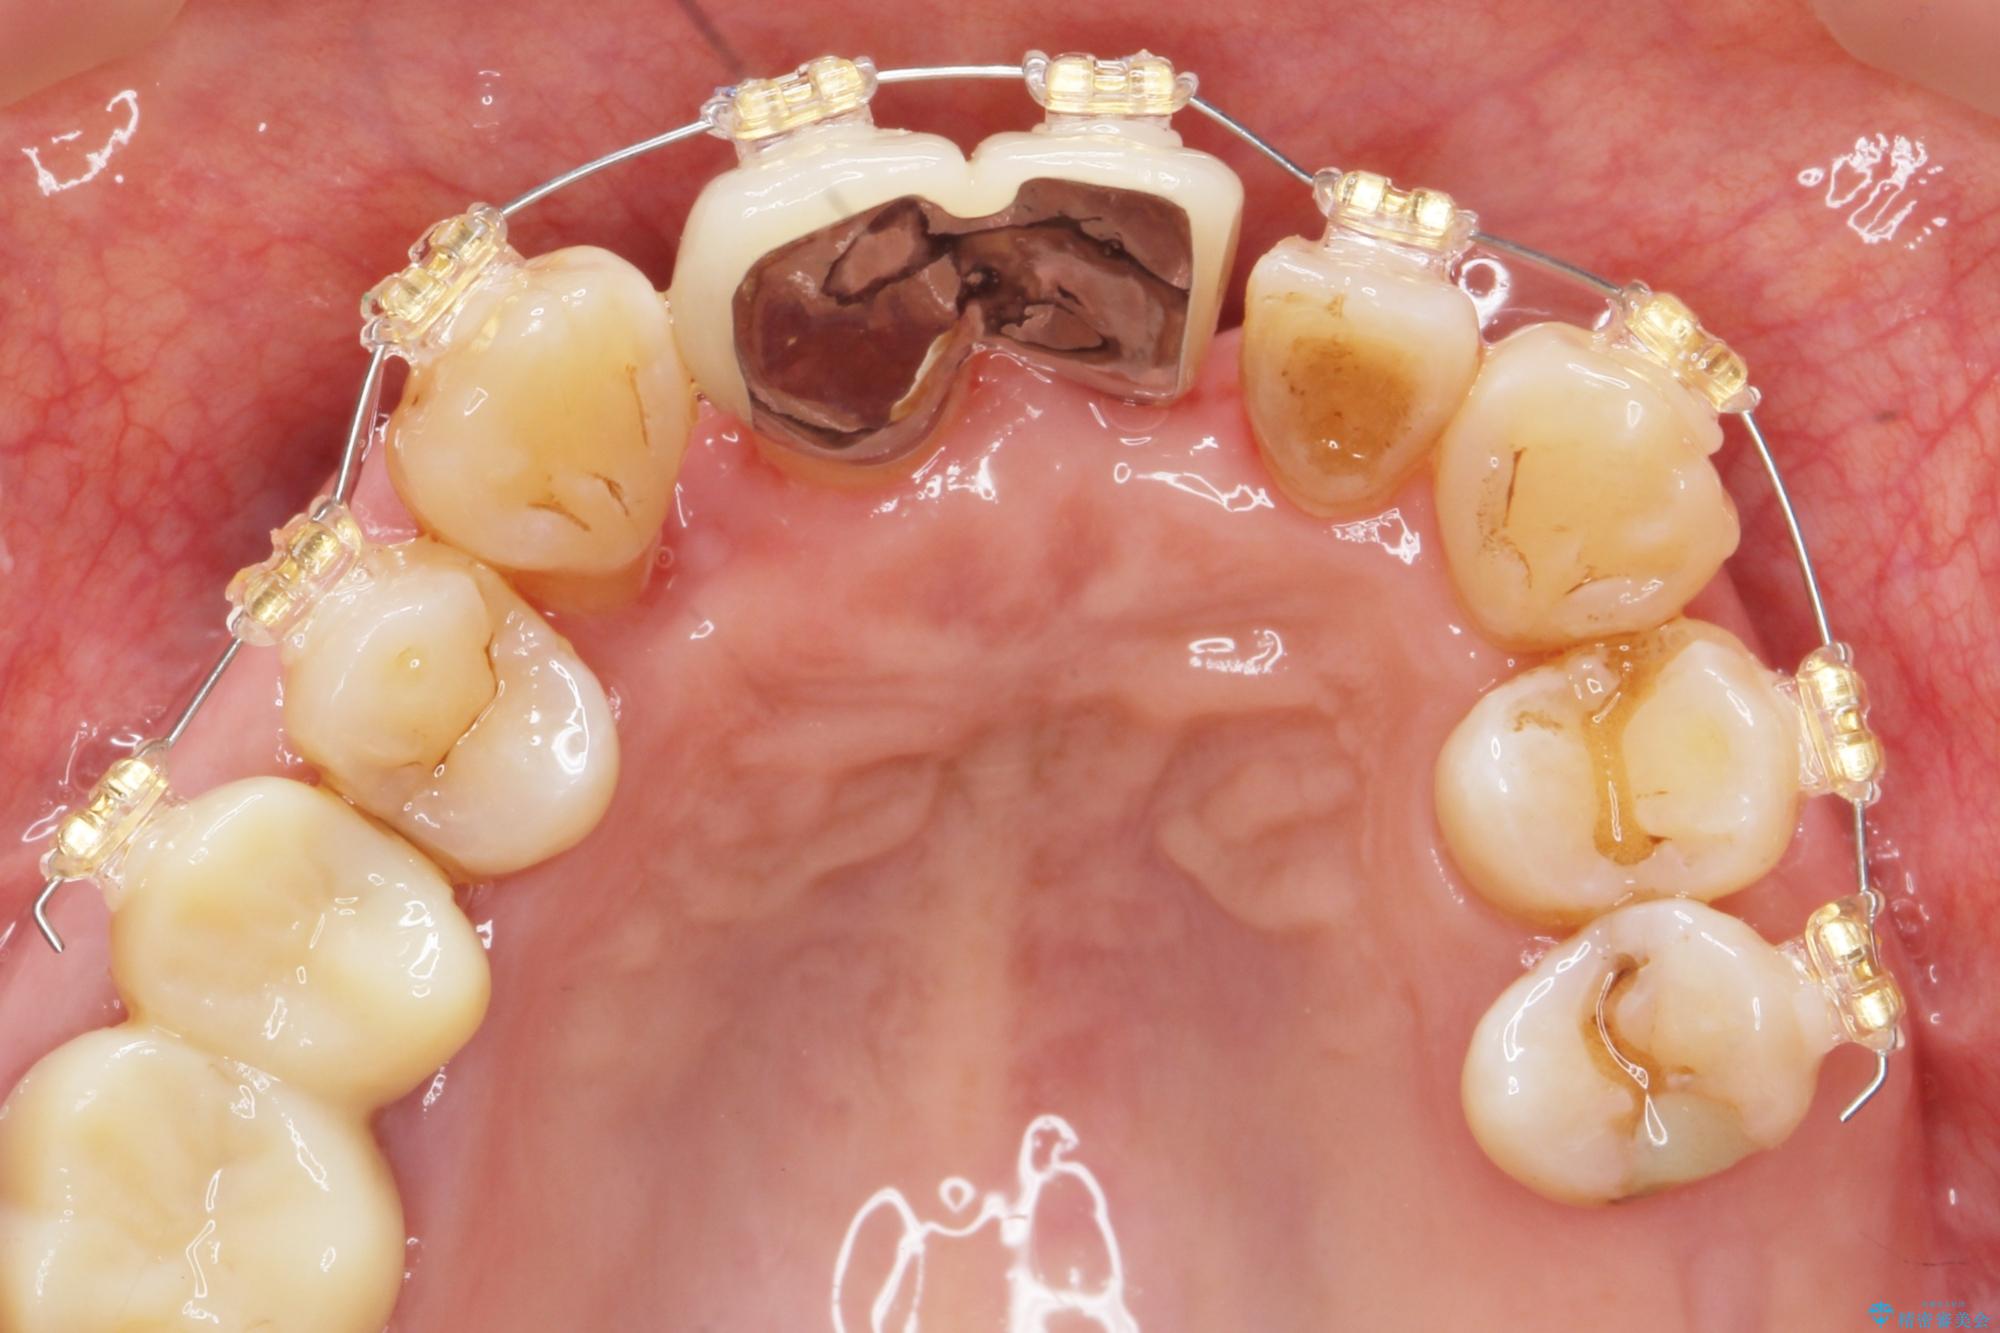

治療中

歯の総合的なマネージメントを行う包括的歯科治療の実践[ 歯周病・矯正・セラミック補綴 ] 治療中画像 歯の総合的なマネージメントを行う包括的歯科治療の実践[ 歯周病・矯正・セラミック補綴 ] 治療中画像 歯の総合的なマネージメントを行う包括的歯科治療の実践[ 歯周病・矯正・セラミック補綴 ] 治療中画像 歯の総合的なマネージメントを行う包括的歯科治療の実践[ 歯周病・矯正・セラミック補綴 ] 治療中画像 歯の総合的なマネージメントを行う包括的歯科治療の実践[ 歯周病・矯正・セラミック補綴 ] 治療中画像 歯の総合的なマネージメントを行う包括的歯科治療の実践[ 歯周病・矯正・セラミック補綴 ] 治療中画像 歯の総合的なマネージメントを行う包括的歯科治療の実践[ 歯周病・矯正・セラミック補綴 ] 治療中画像 歯の総合的なマネージメントを行う包括的歯科治療の実践[ 歯周病・矯正・セラミック補綴 ] 治療中画像 歯の総合的なマネージメントを行う包括的歯科治療の実践[ 歯周病・矯正・セラミック補綴 ] 治療中画像 歯の総合的なマネージメントを行う包括的歯科治療の実践[ 歯周病・矯正・セラミック補綴 ] 治療中画像 歯の総合的なマネージメントを行う包括的歯科治療の実践[ 歯周病・矯正・セラミック補綴 ] 治療中画像